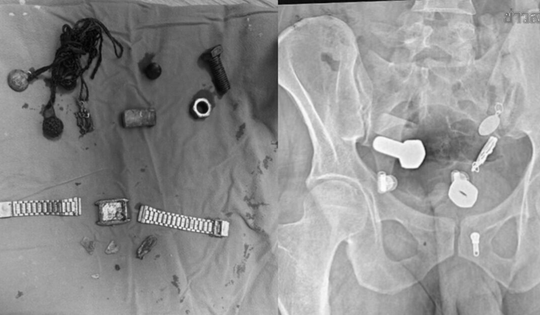

Bác sĩ tháo 'bản án' đeo túi nước tiểu cho hàng nghìn người

Từ cuộc gặp với giáo sư người Mỹ, TS.BS Đỗ Lệnh Hùng tìm ra "chìa khóa" giúp khép lại chuỗi ngày tuyệt vọng ôm túi nước tiểu bên hông của hàng nghìn người bệnh.